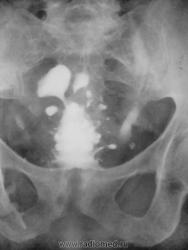

Такое сам вижу в первый раз, это кто то из наших корифеев обнаружил... Теперь смотрим скелет...

Это Вы на лонное сочленение нас направляете?

Но - Симфизит? Периферическая форма болезни Бехтерева?, Что-то ревматоидное или хламидийное наверняка есть, и может быть с дивертикулами связано... Проверить не сможем, но хоть согреемся?

Что-то было у Рейнберга про остит лонных костей, связанный с урологическими заболеваниями у пожилых пациентов. Один раз такое встречала. Вот нашла: Рейнберг, 2 том, стр. 485 (в диф. диангностике раковой костоеды). Может оно?

В подтверждение наличия хр.симфизитов при хр.заболеваниях урогенитальной зоны - женщина, хр.цистит, специфические изменения лонного сочленения....